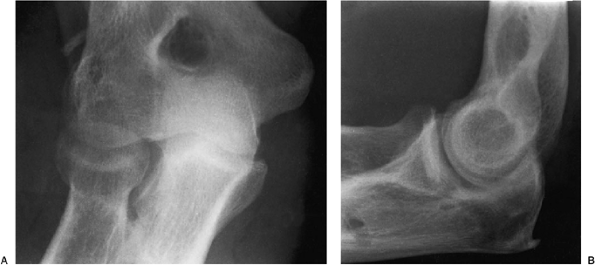

The lateral rotatory stress test showed posterior lateral rotatory

instability, as did the varus stress test (Fig. 15-19). A palmaris longus tendon was harvested (Fig. 15-20) and the lateral complex was reconstructed as described earlier (Fig. 15-21). One year later her motion was normal and the joint was stable (Fig. 15-22).

Figure 15-19. A,B: Stress radiographs reveal a deficiency of the lateral collateral ligament with varus and posterolateral rotary stress.